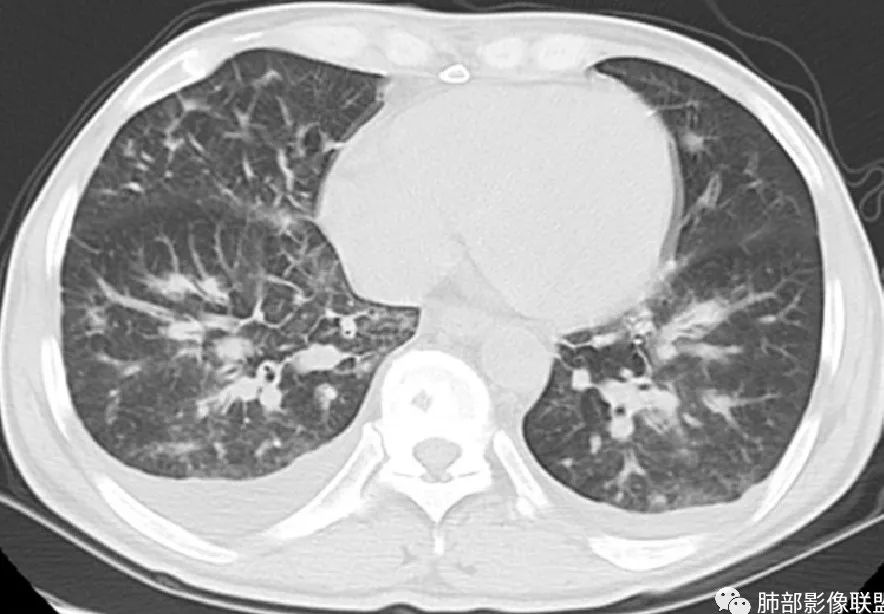

中年男人患者,发热纳差,乏力伴皮疹1月,体温38.4℃,全身暗紫色丘疹,CD4明显降低,双肺多发斑片结节影,周围伴有晕征,有沿支气管血管束分布趋势,无坏死,无空洞,淋巴结增大不明显,考虑机会性感染性病变,马尔尼菲篮状菌病?结核?鉴别淋巴瘤,血管炎(GPA)。

中年男性,发热、纳差、乏力、皮疹1月,,全身散在暗紫色丘疹,CD4明显减少,双肺散在多发斑片状、结节状密度增高影,边缘稍模糊,以双肺下叶较多,沿支气管血管束播散征象,小叶间隔增厚,叶间裂及双重胸膜腔少量积液,考虑马尼可能大,建议真菌,比如曲霉?念珠菌等

周一晚读病例:男性45岁,发热、纳差,全身散在暗紫色皮疹,结合CD4,符合HIV;肺部影像表现:两肺散在实性结节及磨玻璃密度影,实性结节伴晕征,部分沿支气管血管束分布,支气管血管束增粗,以两肺下叶为著,类似火焰征,双侧胸腔少量积液;首先考虑卡波西肉瘤,鉴别淋巴瘤增值性病变,淋巴瘤样肉芽肿/淋巴瘤,最后挂上马尔尼菲青霉菌病。

中年男性,发热、全身散在暗紫色丘疹,查CD4+T细胞64个/ul,临床信息提示AIDS并发卡波西肉瘤;CT提示双肺多发实性结节影及毛玻璃结节,部分呈点晕征,右上肺大姐姐边缘膨隆、分叶伴晕;双下肺结节沿支气管血管束分布,中轴间质增粗,部分支气管堵塞,叶间裂结节状增厚,部分结节胸膜下分布,可疑局部小叶间隔增厚,肺部病变呈淋巴分布特点,结合临床肺部病变考虑肺卡波西肉瘤,鉴别淋巴瘤。

2.本例双肺小叶间隔增厚明显,多发结节影及片状实性密度影,沿血管支气管束分布为主,两侧较为对称,病灶多环以磨玻璃晕,边界不清。

双侧胸腔少量积液。双肺门及纵隔未见明确肿大淋巴结,纵隔结构间隙模糊。

3.有学者将这种具有沿双肺支气管束分布的实性密度片影描述为“火焰征”,认为具有一定特征性,单就影像表现而言,这种影像表现也可以见于其他病损或多种病理改变的叠加。

如马尔尼菲篮状菌感染,HIV患者总会联想到它!同样可以出现双肺多发结节影、片影及磨玻璃影,结节影边界也可以较为清楚(甚至可以有点类似结核那种肉芽肿结节),磨玻璃影常见于灶周出血等等。尽管临床实践中马尔尼菲篮状菌感染似乎更多表现为淋巴增大及网质内皮系统损害(如肝脾改变)以及较特有的带有脐凹的皮疹等等。

1.结节型:两肺沿支气管血管束分布的结节影,呈火焰状或星芒状、挂果征,局部周围出血磨玻璃影(肺泡出血或水肿)。

2.支气管血管束增粗型:

肺门周围支气管壁呈“套袖样”改变。

3.肺炎渗出型:

斑片渗出影,部分融合呈“火焰样”,同时有火焰样结节,小叶间隔增厚等表现。

还可以有纵隔及腋下淋巴结增大,胸腔积液等表现。